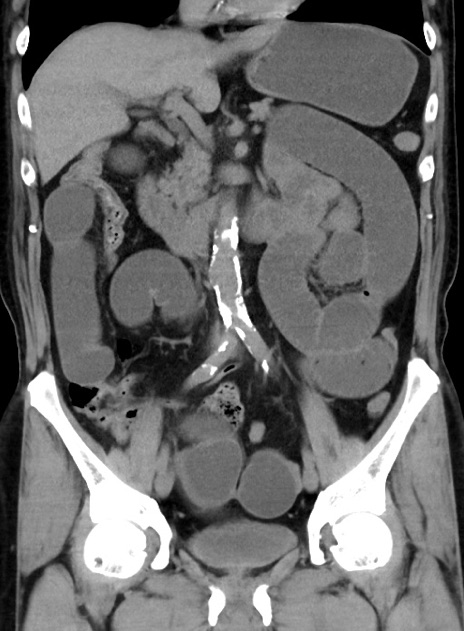

症例38(冠状断像)

【症例】70歳代 男性

【主訴】腹痛・嘔吐

【現病歴】昨晩より、嘔吐・腹痛あり。今朝になっても嘔吐あり。来院。

【既往歴】心臓バイパス手術、開腹胆摘、腸閉塞

【身体所見】BP 107/71mmHg、HR 116/min、腹部:平坦、軟、下腹部に軽度圧痛あり。反跳痛なし。

【データ】WBC 15100、CRP 0.32